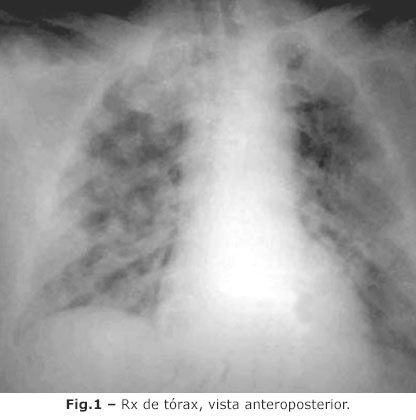

Una de las formas clínicas de la COVID-19, es la neumonía bilateral, que en sus presentaciones más complejas, se asocia con hipoxemia grave, y SDRA,(8) radiológicamente caracterizado por lesiones pulmonares multifocales bilaterales, según reportes de China y Corea.(4) Otras complicaciones descritas, son la sepsis y el choque.(1)